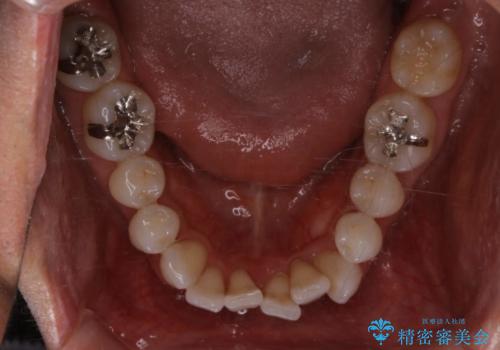

右上の前から2番目の歯が引っ込んで、下の前歯にはガタガタがありました。

上下の歯と歯の間を少量ずつ削りスペースを作り、インビザラインにて並べる計画としました。